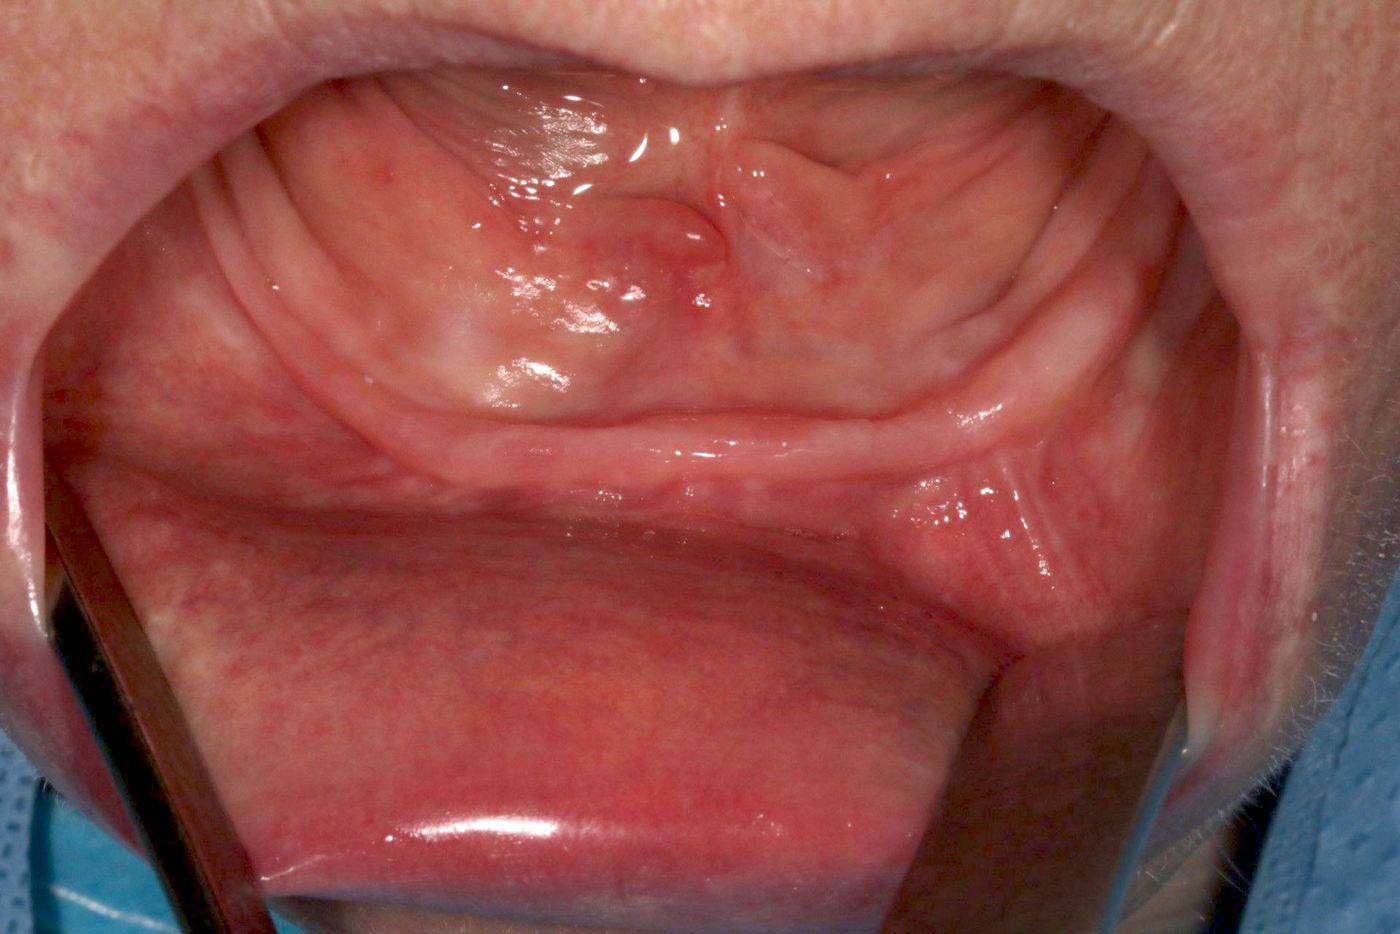

Patient, a 66-year-old lady in good health and with a thin mandibular ridge. Her main complaint was the poor retention of the prosthesis, causing her pain and discomfort when chewing properly while eating. The same retention problem would also make her very uncomfortable at social events, as she was afraid of the prosthesis slipping when she laughed.

Treatment Planning